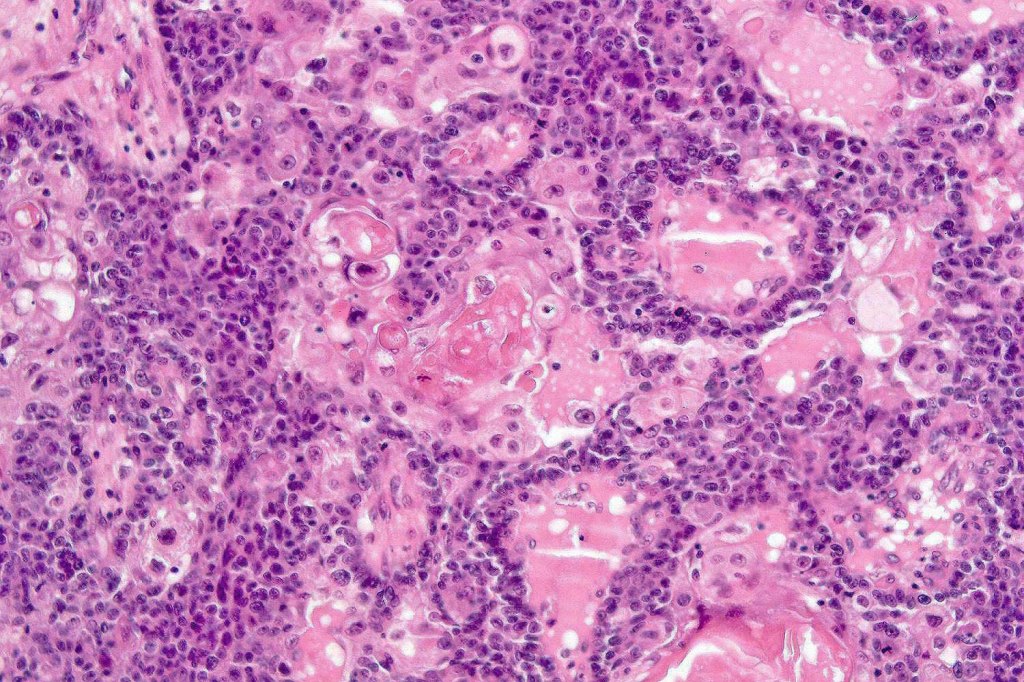

•Well differentiated lobular growth pattern though to a poorly differentiated tumor often showing a diffuse, infiltrating border which may extend into the subcutaneous fat

•Comedo type necrosis commonly present

•Tumors are composed of an admixture of darkly staining basaloid cells with hyperchromatic or vesicular nuclei and more obvious sebaceous cells with eosinophilic, bubbly, multivacuolated cytoplasm frequently indenting the nucleus (scalloped)

•Often mitoses are numerous and abnormal forms evident

Sebaceous carcinoma from a patient with Muir-Torre syndrome kindly shared by Dr. Antonina Kalmykova.